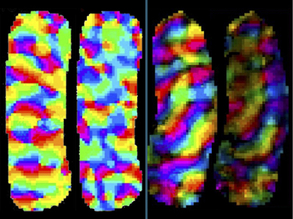

Mind Maps